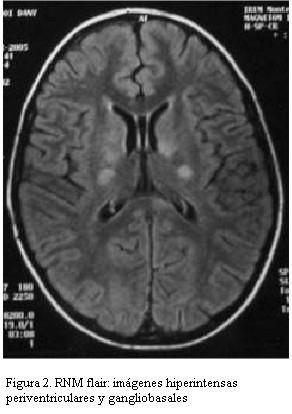

RNM: áreas hiperintensas en la secuencia T2 y Flair en: hemisferio cerebeloso izquierdo subcortical, tronco encefálico a nivel protuberancial y de pedúnculos cerebrales, en región subtalámica bilateral y gangliobasal izquierdo, lóbulo parietal subcortical y paraventricular derecho (figuras 1 y 2).

La resonancia magnética nuclear es el examen de elección para confirmar estas alteraciones, revelando en el neuro-Behçet tres patrones característicos: una fase inicial en la que se evidencian focos de hiperintensidad en T2 a nivel de tronco cerebral, gangliobasal y hemisferios cerebrales; una fase intermedia con mayor inflamación que causaría edema y efecto de masa que puede regresar espontáneamente o con tratamiento inmunosupresor, pudiendo encontrar focos de microhemorragia con hiposeñal por los depósitos de hemosiderina, y finalmente en la fase crónica predominan imágenes de atrofia especialmente en tronco encefálico. El seguimiento neuroimagenológico evidencia regresión o desaparición de las lesiones parenquimatosas a largo plazo (meses a años) (19).